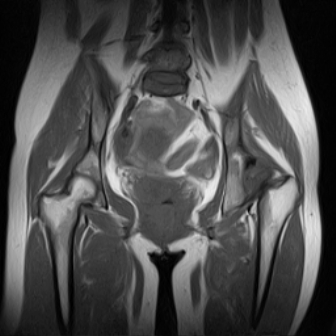

片子不全,应该是左侧股骨头无菌坏死,右侧似乎没问题,到正规医院治疗,千万别看广告去小医院,吃中药什么的,都是骗人的(说了也白说,百分百都得让人骗点钱才甘心。)

应该是左侧股骨头无菌坏死